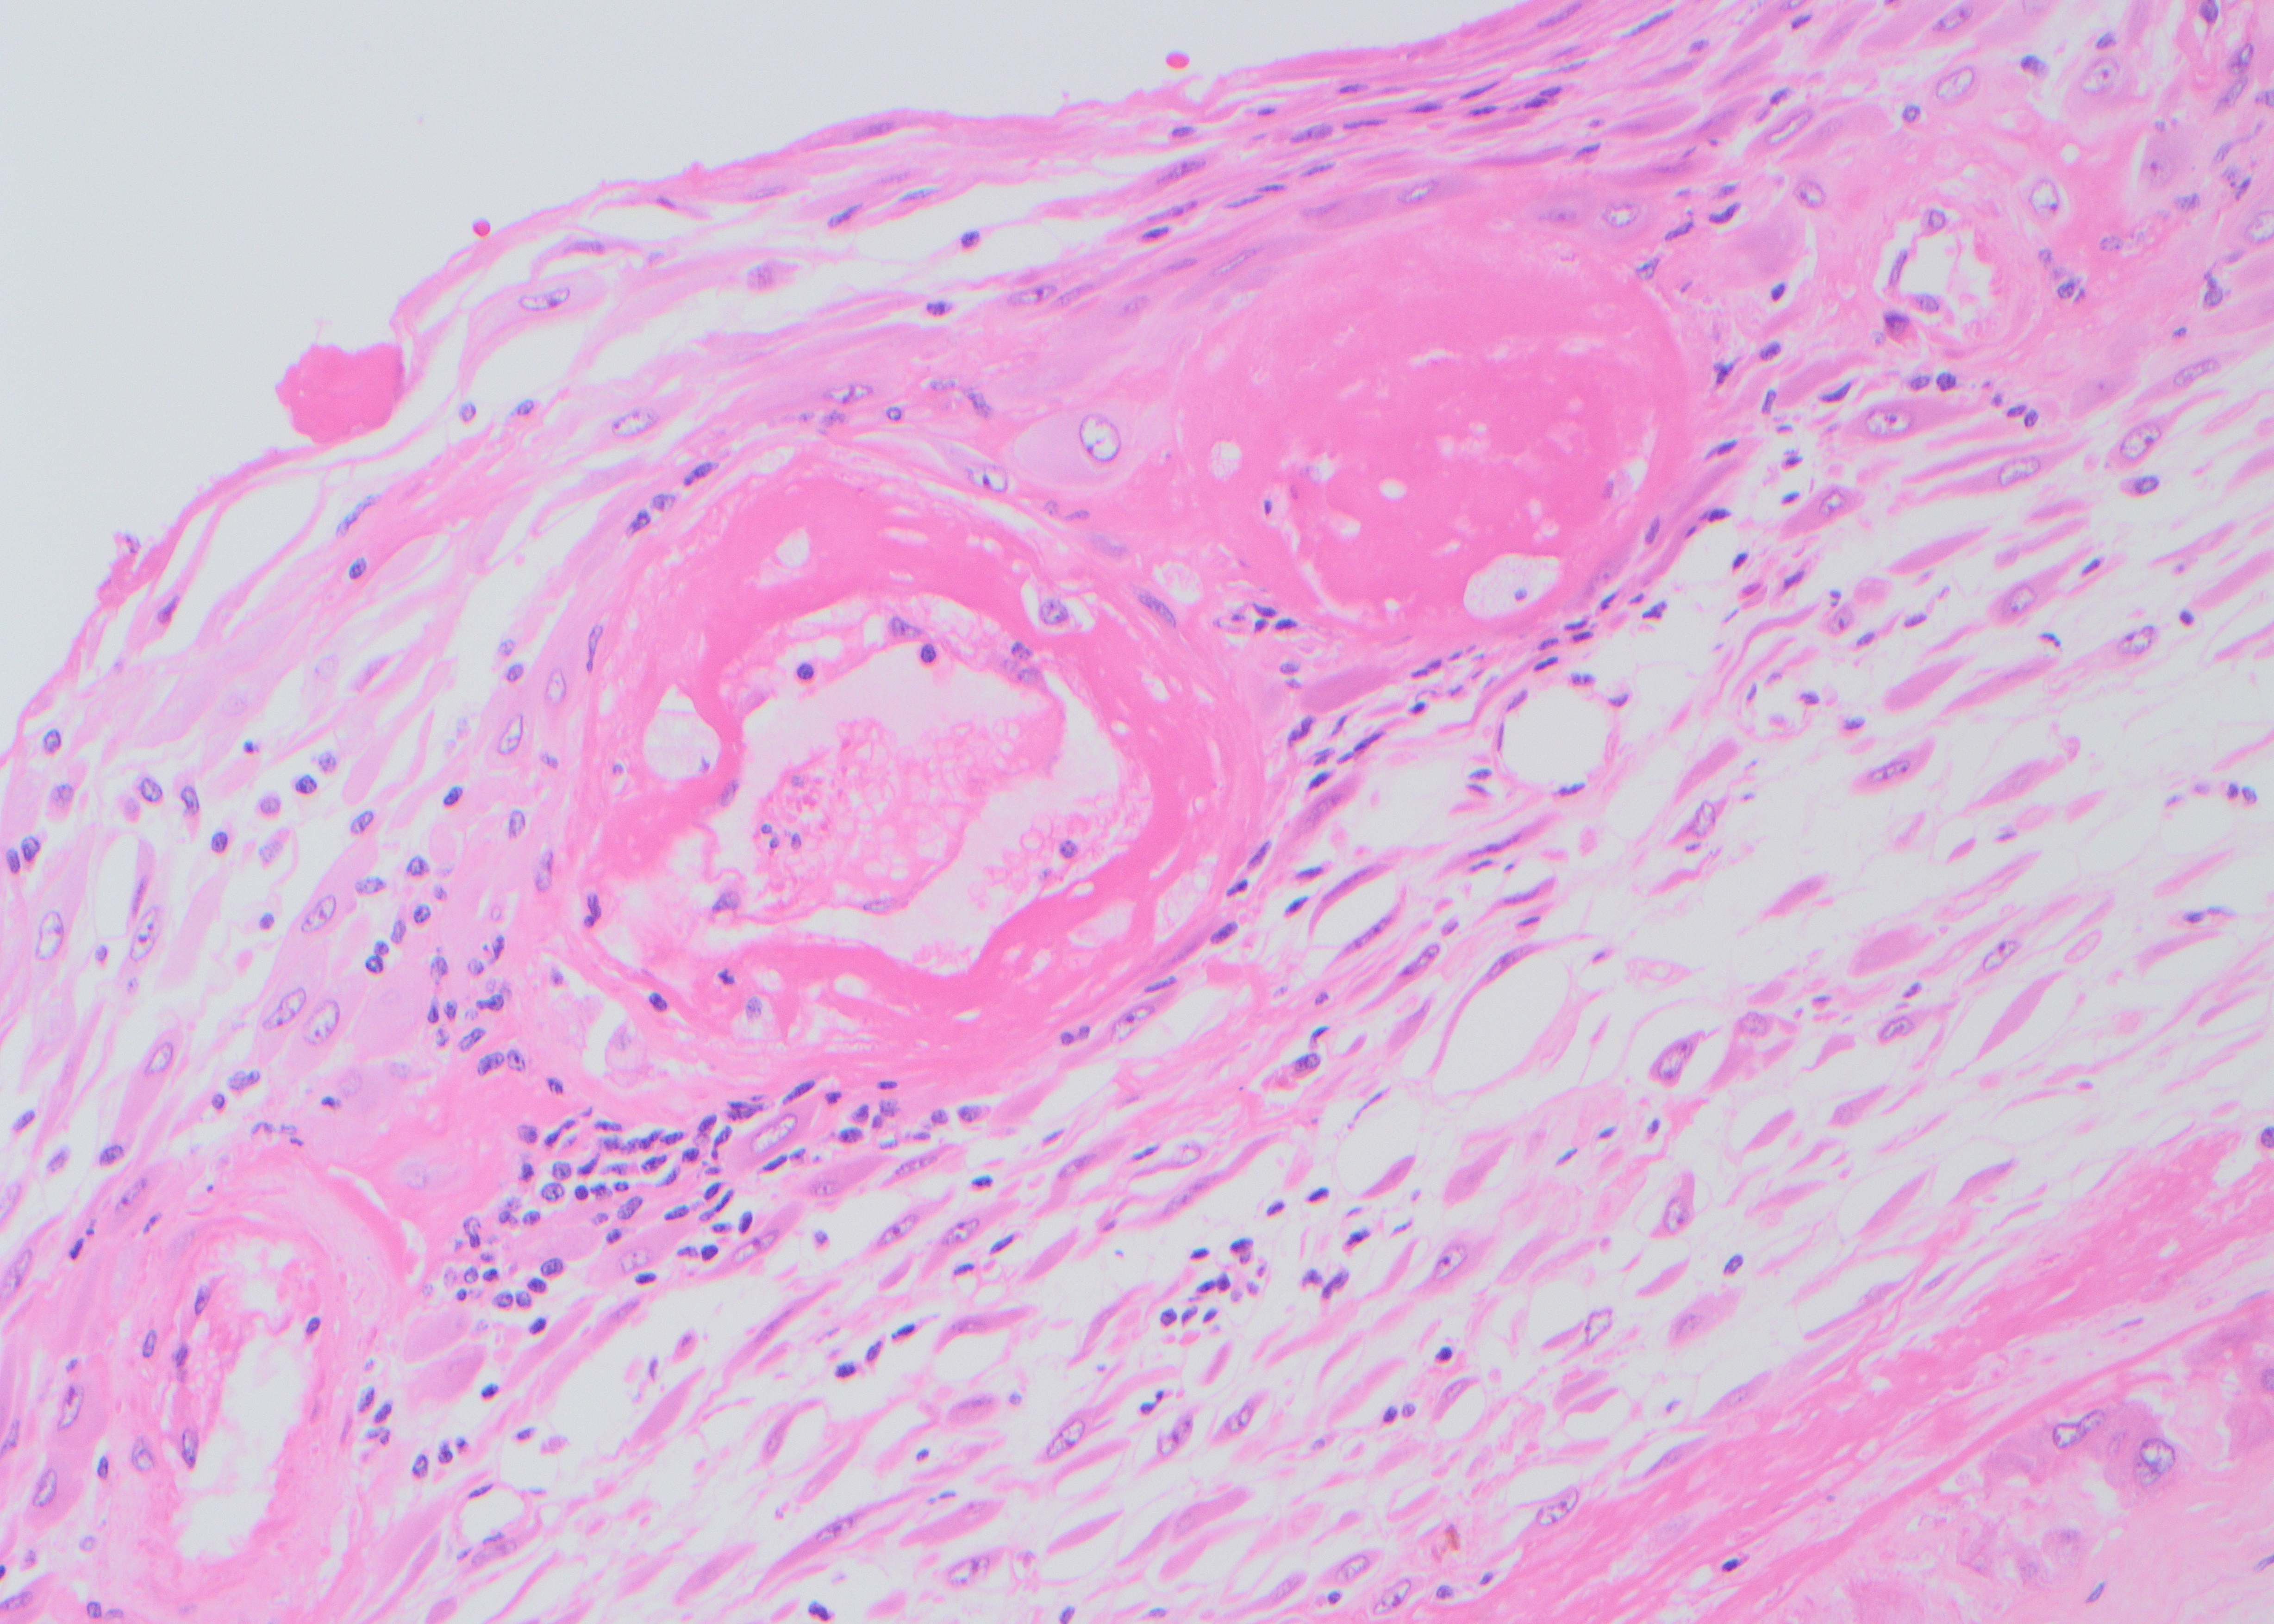

Case History:

A 64 year-old man with history of clear cell renal cell carcinoma s/p nephrectomy (2021) presents with scrotal pain and firmness. Ultrasound reveals a 2 cm solid lesion. Serum tumor markers (hCG and AFP) were normal. The tumor was negative for SALL4, OCT3/4, AFP, and showed focal patchy positivity for pancytokeratin (focal). PAX8 was weakly positive. Additional stains are displayed in the pictures.